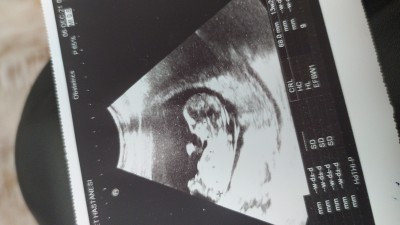

Çok merak ediyorum içinize ne doğuyor ben erkek hissediyorum ama  15+4

Ultrasona bakarak anlayamadim şu an ama erkek biraz erken belli oluyor ben birini 12+3 de öğrendim birini 13 haftada gayet netti :)) göstermiyor olabilir seninki benim icimden kız geçti

Göstermemesi değil canım bulunduğum şehirdeki ultrason cihazları eski doktorum 20 haftadan önce göremeyiz cihazlarımız uygun değil dedi

Öyle mi o zaman bisey diyemem canm bacağı kapalı ama yan yatıyor nasıl bilecez burdan ama icimze geleni soruyorsan kız geçti benim icimden :) bide muayneye gitmeden tatlı bişeyler ye hareketlensin bebek belki erken görür dr